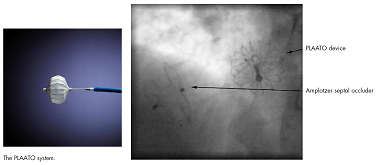

自从LAAC技术问世后,ASD和LAA的同期封堵便已在临床上出现。2006年德籍华裔医师余江涛曾在Heart杂志报道过一例采用PLAATO封堵器和AGA公司的房间隔缺损封堵器对一位76岁患者实施同期封堵,手术过程顺利,第二天患者出院(图3)。随着watchman和ACP封堵器的问世,这类同期治疗病例逐年增加,类似的个案报道有很多。国内长海医院、沈阳军区总院和西南医院等多家医院也多次在学术会议上报道过类似病例(图4)。在完成LAAC后,WATCHMAN封堵器和LACBES封堵器的输送鞘管均可直接用于房间隔缺损封堵器的植入,节省了手术时间和费用。更重要的是,笔者认为,同期封堵技术的顺利开展,也提出了一个值得大家关注的,可能成为经导管左心耳封堵的新适应症人群,即高龄房间隔缺损合并房颤的患者。

图3 PLAATO封堵器+ASD封堵器